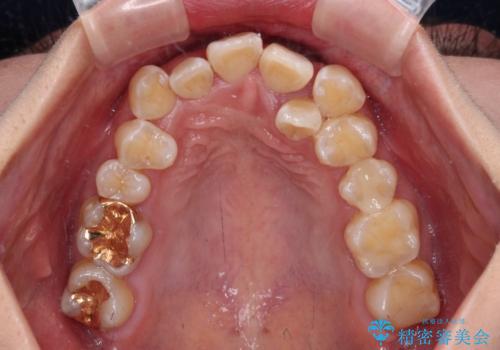

- 前歯1本が後ろ側に隠れてしまうほどのデコボコを気にして来院された患者様です。

前歯のデコボコが顕著なのはもちろんですが、左右ともに奥歯の咬み合わせに問題があり、上顎臼歯が前方位にある状態でした。

上顎は左右の第一小臼歯2本を、下顎は左右第二小臼歯2本を抜歯することで、奥歯の咬み合わせを改善しながら、デコボコを解消していくこととしました。